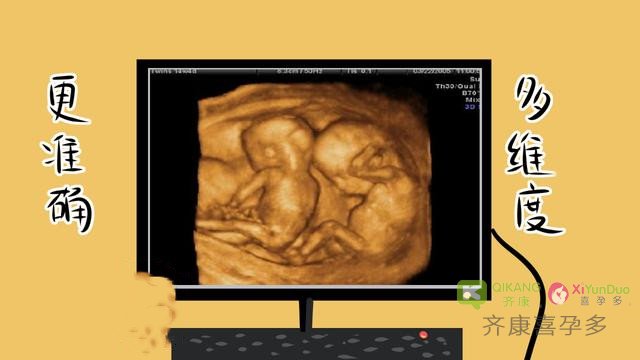

孕妈妈在孕早期或多或少都听说过四维彩超,这是宝宝人生中的第一张照片,通过四维彩超图像,能够清晰的看到自己腹中宝宝的长相。当然,最主要的是通过医学上四维彩超的检查,能够对胎儿的各项发育情况作出判断,是防止胎儿畸形的最全面的检查。关于四维彩超无论是自然受孕还是试管婴儿受孕,都是要做四维彩超,因为四维彩超是防止胎儿在母体发育缺陷的一项重大排畸,所以四维现在产检项目中必不可少的一项检查项目。

最后齐康喜孕多再次提醒大家:四维超彩超与普通B超相比,有了实时动态的效果,准爸爸、准妈妈可以通过屏幕亲眼目睹宝宝在妈妈肚子里运动、呼吸、吞咽、打哈欠、伸舌头等生理活动,非常直观。更重要的是能更准确的排畸,所以无论是自然受孕还是第三代试管四维都是产检项目中必不可少的一项重要的检查。